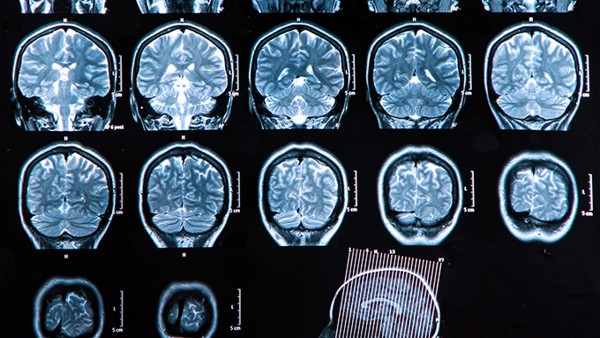

脑梗死也被称为缺血性脑卒中,患者会出现局限性脑组织缺血坏死或软化的情况,从而导致脑部的血液循环出现障碍使得相关的器官组织缺血和缺氧。脑梗塞是临床上常见的脑血管疾病,约占急性脑血管疾病的70%,多见于中老年人。通常,脑梗塞与大动脉粥样硬化、小动脉闭塞、心源性栓塞等多种因素有关。此外,烟雾病、高血压、心脏病、糖尿病等疾病也可能诱发脑梗塞。

1、临床上,根据梗死发生的部位,脑梗死可分为前循环梗死、后循环梗死、前循环梗死、间隙梗死等多种类型。在发病初期,大部分患者意识清醒,中期都会出现四肢瘫痪、昏迷、意识障碍、应激性溃疡等症状,在晚期可能会引发脑疝等严重并发症甚至危及生命导致脑死亡。